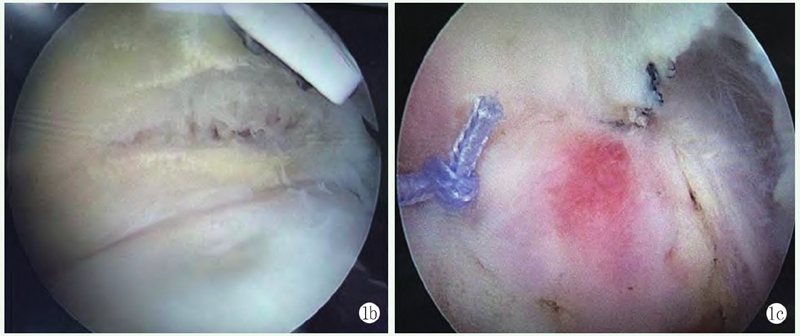

影像学检查:X线片显示肩峰外缘增生,肱骨头上移,肩峰-肱骨距离短缩(图2a)。MRI示:右冈上肌全层撕裂并回缩,轻度脂肪浸润,肱二头肌长头腱断裂(图2b),诊断为右肩袖损伤。

图2a: 术前 X 线片示肩峰外缘增生,肱骨头上移,肩峰-肱骨距离短缩;2b: 术前 MRI 显示右冈上肌全层撕裂并回缩,轻度脂肪浸润,肱二头肌长头腱断裂